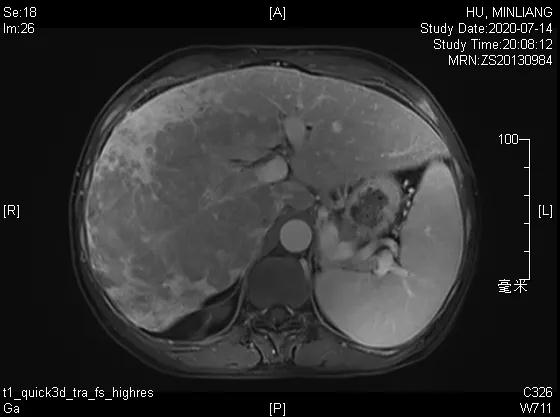

肝脏弹性超声:12kPa。腹部MRI平扫+增强:肝巨块结节性HCC(最大径18.4cm)伴肝内多发转移(最大径3.5cm),肝右静脉广泛癌栓形成;肝硬化伴门脉高压、脾大、少量腹水;肝囊肿;双肺多发转移。胸部CT平扫:两肺多发转移,两肺气肿伴肺大泡,两肺散在慢性炎症,右侧少量胸水。

Δ肝脏MRI,最大肿瘤18.4cm